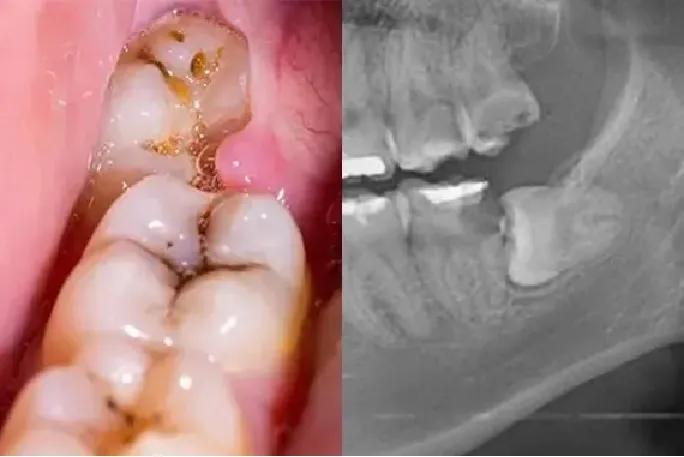

جراحی دندان عقل نهفته و نیمه نهفته در سقز _ آنچه باید بدانید

بسیاری از افراد در سنین نوجوانی و جوانی با مشکلی به نام “دندان عقل نهفته یا نیمه نهفته” مواجه میشوند. این مشکل، اگر به موقع تشخیص داده نشود، میتواند درد، التهاب، پوسیدگی سایر دندانها و حتی آسیب به فک را به دنبال داشته باشد. شهر سقز نیز از این قاعده مستثنا نیست؛ بسیاری از ساکنین […]